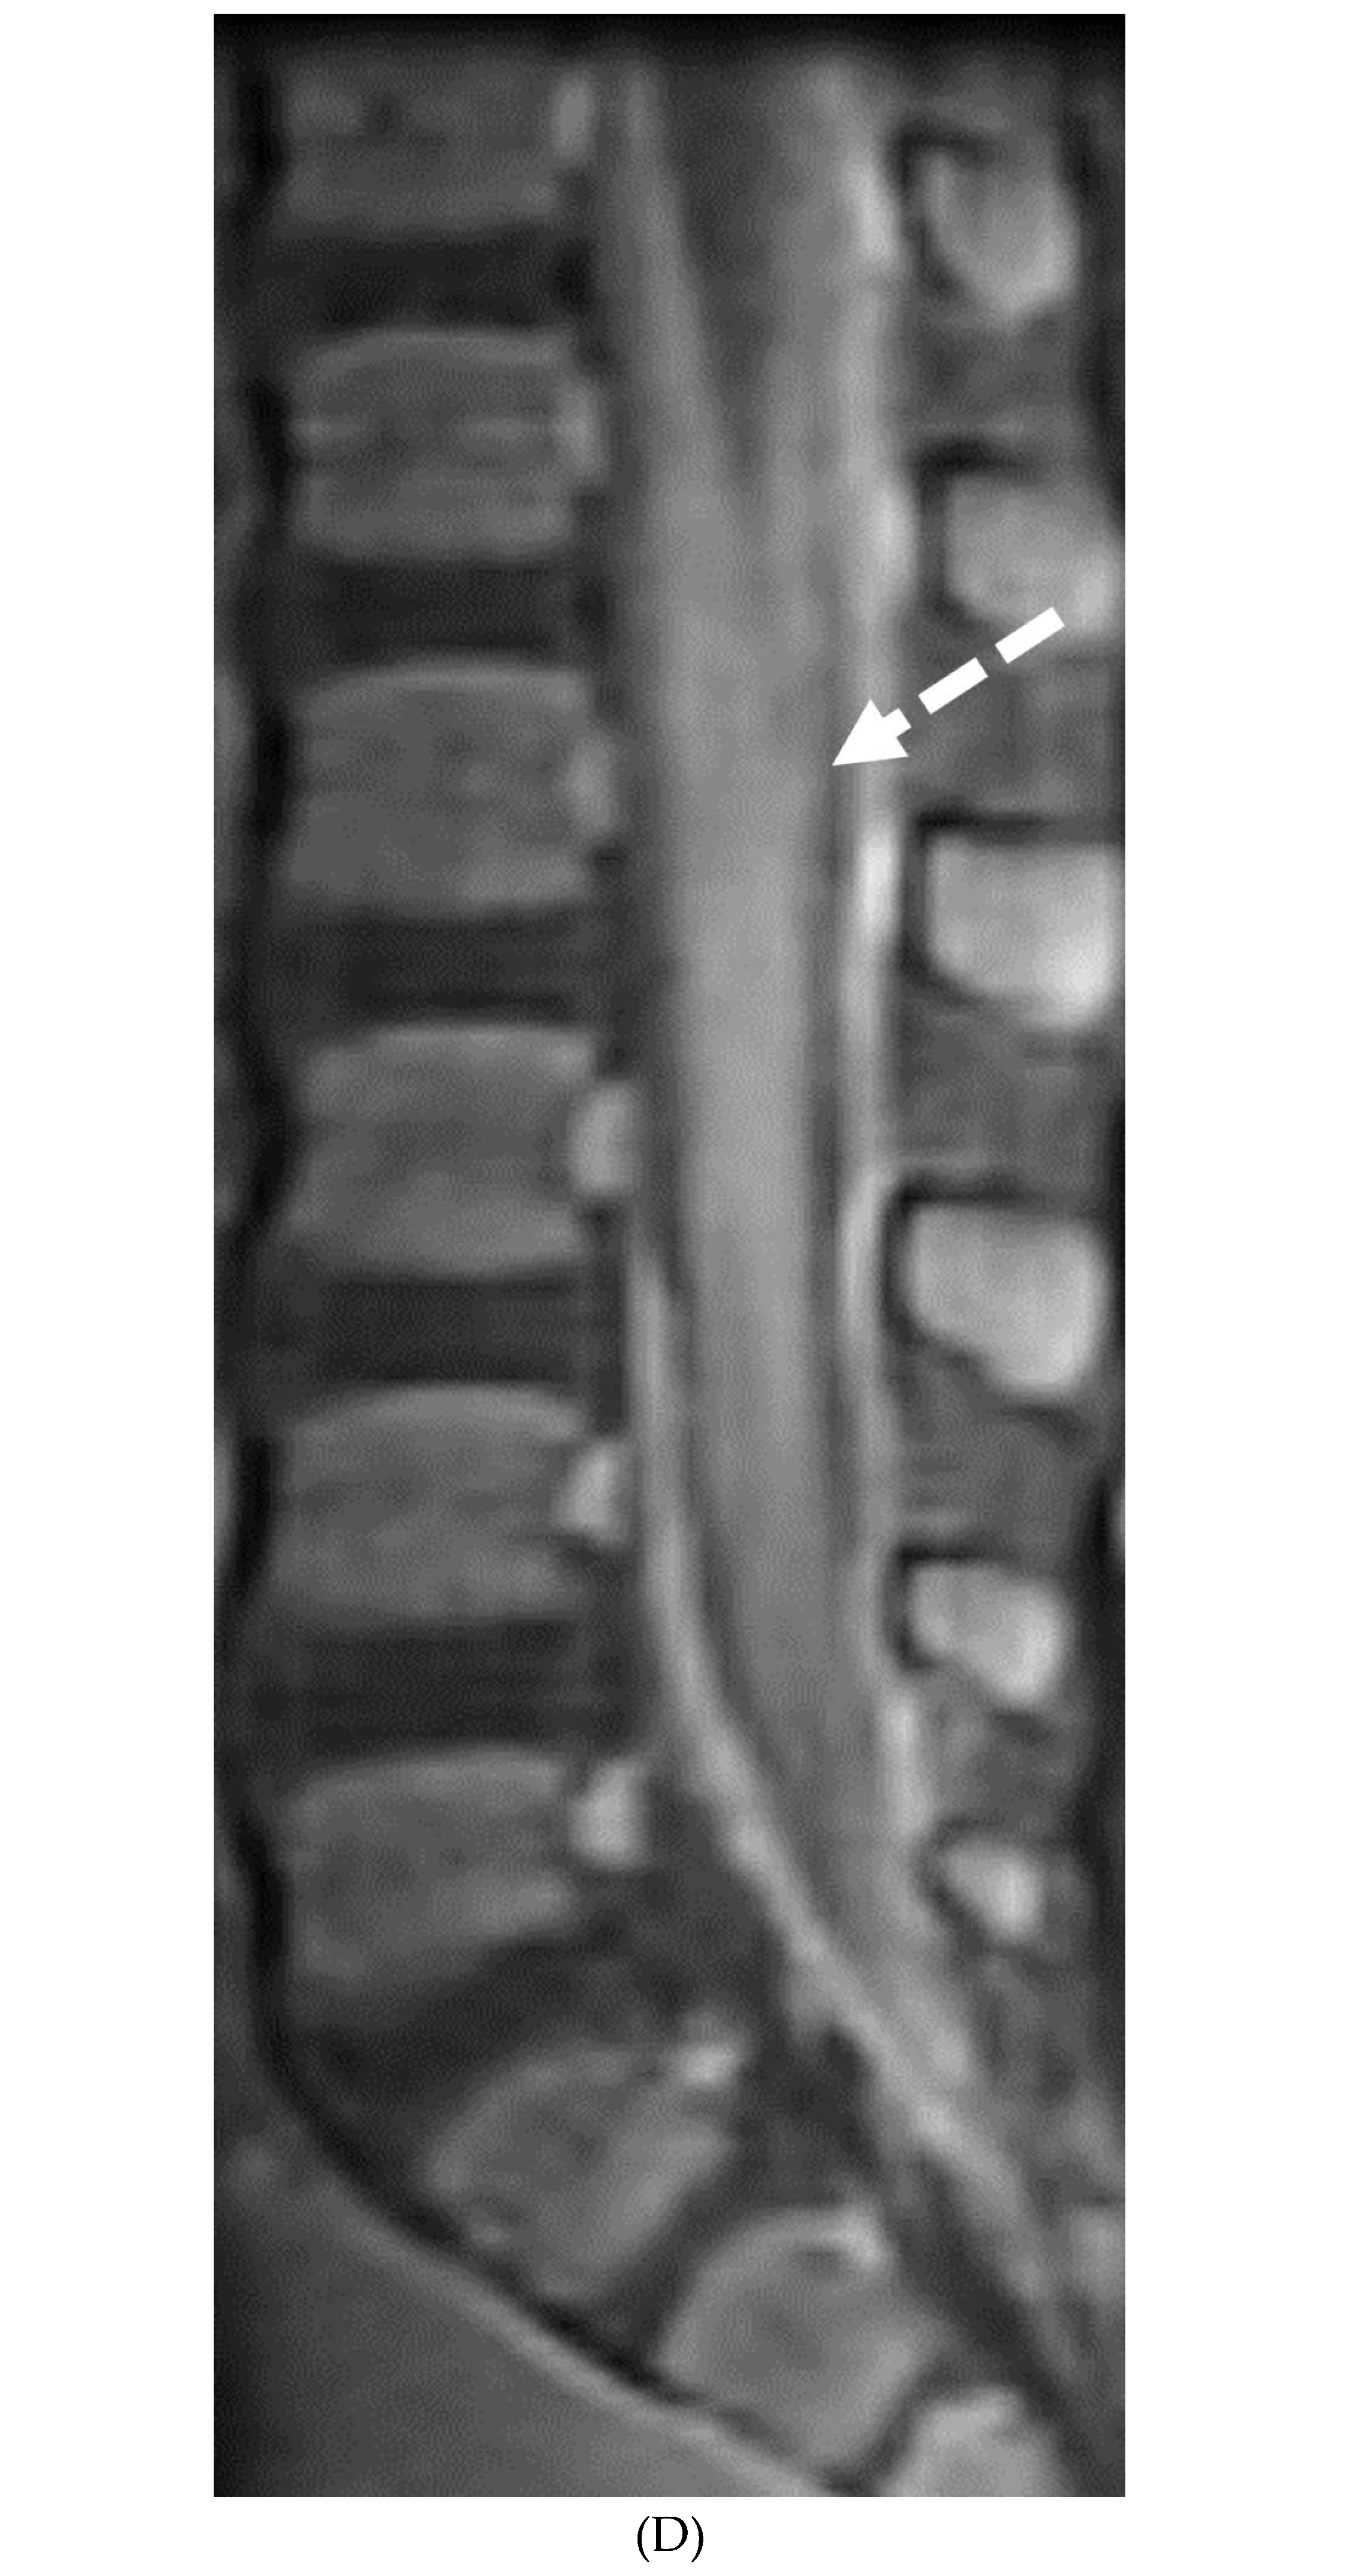

- Alkan O, Yildirim T, Tokmak N, Tan M. Spinal MRI findings of guillain-barré syndrome. J Radiol Case Rep. 2009;3(3):25-8. Epub 2009 Mar 1. PMID: 22470650; PMCID: PMC3303301. [CrossRef]

- Byun WM, Park WK, Park BH, Ahn SH, Hwang MS, Chang JC. Guillain-Barré syndrome: MR imaging findings of the spine in eight patients. Radiology. 1998 Jul;208(1):137-41. PMID: 9646804. [CrossRef]